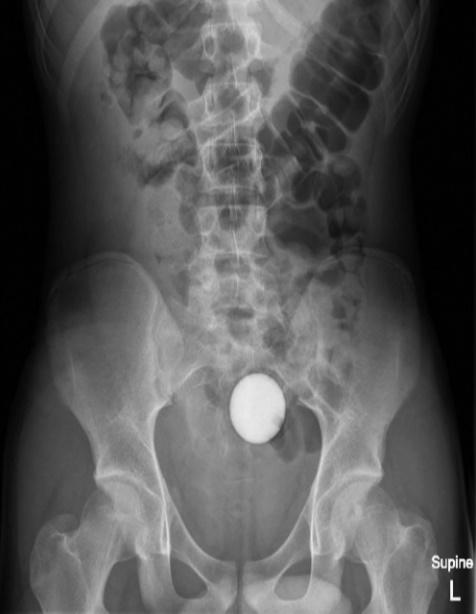

X光顯示,一顆球體卡在腹腔內。(外科病例報告) X光顯示,一顆球體卡在腹腔內。(外科病例報告)

24小時後,醫生再為少年照X光,但高爾夫球依然卡在腹腔,但少年的家屬不願意再讓少年接受入侵性治療,因此醫生轉開大量瀉藥,令少年最終「屙」出這顆高爾夫球,少年的腸道及胃道亦沒有受損,身體狀況一切正常,隨後就讓少年出院,但也警告他「不要再將東西塞入肛門直腸」。醫師除了在期刊上公開這起病例,亦在報告中強調,如果有異物進入病患體內,若病患的腸胃道正常的情況下,建議治療方法首選是瀉藥,以用最自然的方法將異物排出。